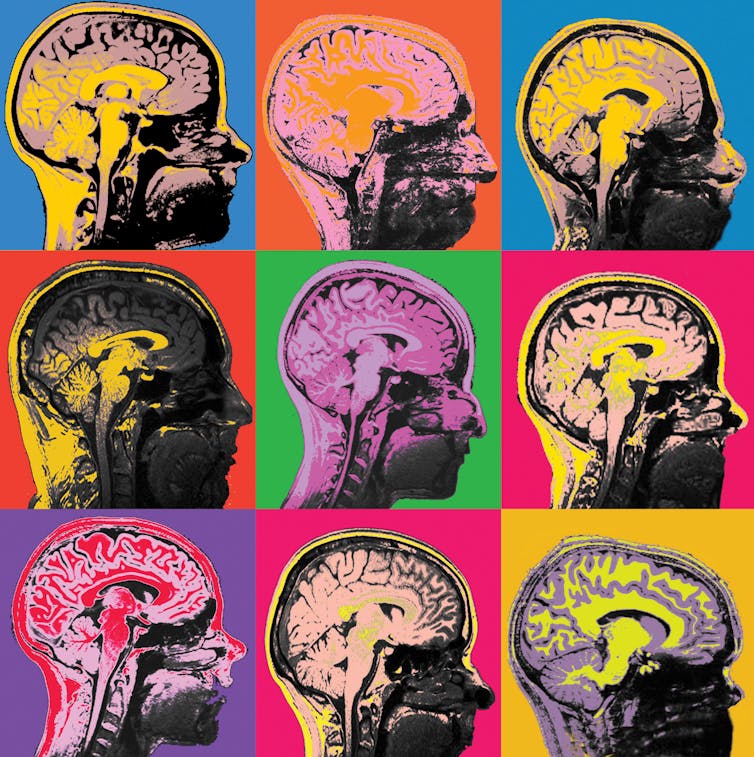

As neuroscience becomes increasingly of public interest, researchers are striving to make their findings accessible, with parallels to the pop art movement. These are MRI images of the human brain.